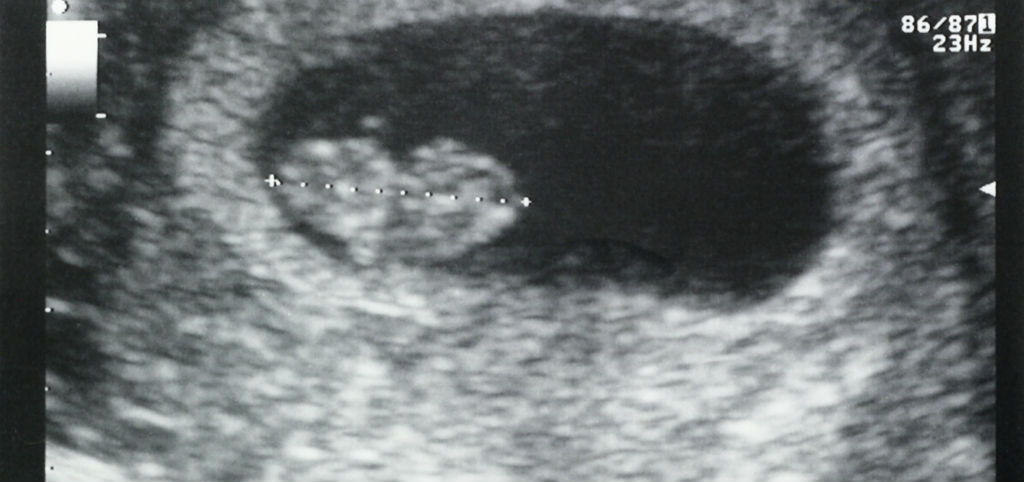

En este estudio, un equipo de investigación de ISGlobal describe el caso de una mujer en su séptima semana de embarazo que viajó a República Dominicana, donde desarrolló síntomas compatibles con infección por zika. A su regreso a España, un examen de rutina reveló la muerte del feto (que se estima ocurrió a la semana 8 de gestación). El equipo pudo aislar el virus en la placenta  y tejido embrionario. La mujer tenía anticuerpos contra el virus, y se pudo además detectar virus en sangre (por métodos moleculares) hasta un mes después de la aparición de los síntomas.